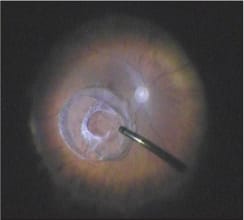

Figure 1. Intraoperative appearance of luxated capsular bag-intraocular lens-capsular tension ring complex.